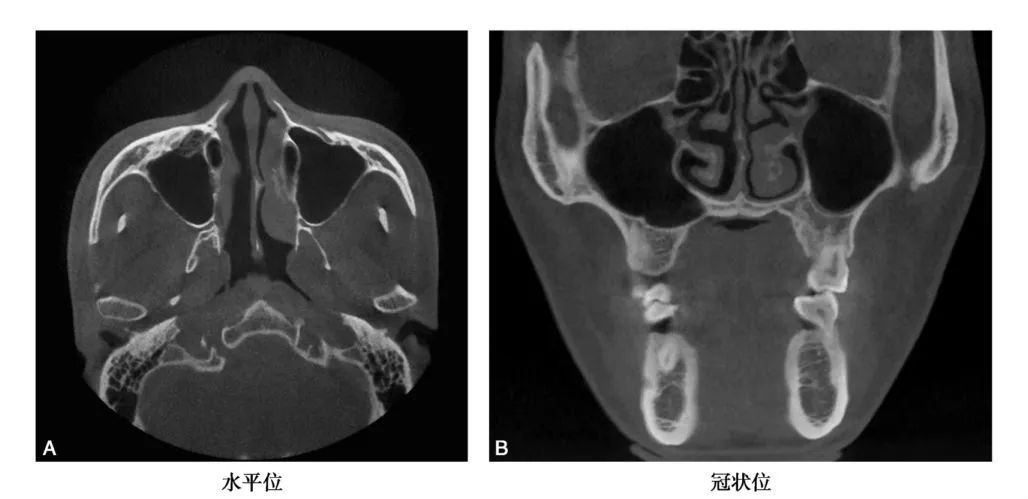

CBCT图像显示上颌窦是一个形状不规则,大小也不尽相同的腔,矢状位上是一由上、下、前、后壁构成的类似四方形或者梯形结构(图1-1-12)。冠状位上可见上颌窦上、下、内、外壁,形态多不规则(图1-1-13)。水平位可见前外、后外、内壁,中份多为类三角形,两端形态多不规则(图1-1-14)。上颌窦腔的容积为9. 5~20ml,平均为14. 75ml。不同人上颌窦形状和大小差别较大,同一个体双侧上颌窦形态基本对称(图1-1-15),但也存在同一个体两侧上颌窦形状和大小有差异(图1-1-16)。

A、C.可见窦腔形态不规则; B.窦腔形态类似三角形